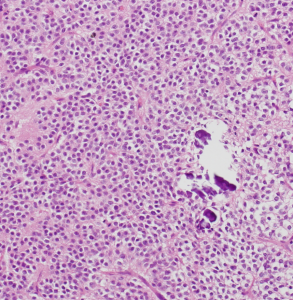

病理所見

石灰化(画面右側の紫色の部分)とともに、均一な大きさの円形の核を有する腫瘍細胞が敷石状に配列している。

核周囲は明るく抜けている。腫瘍細胞間には細い血管が介在し、腫瘍細胞を区画している。

腫瘍細胞間には好酸性(ピンク色)の細線維性基質が認められる。